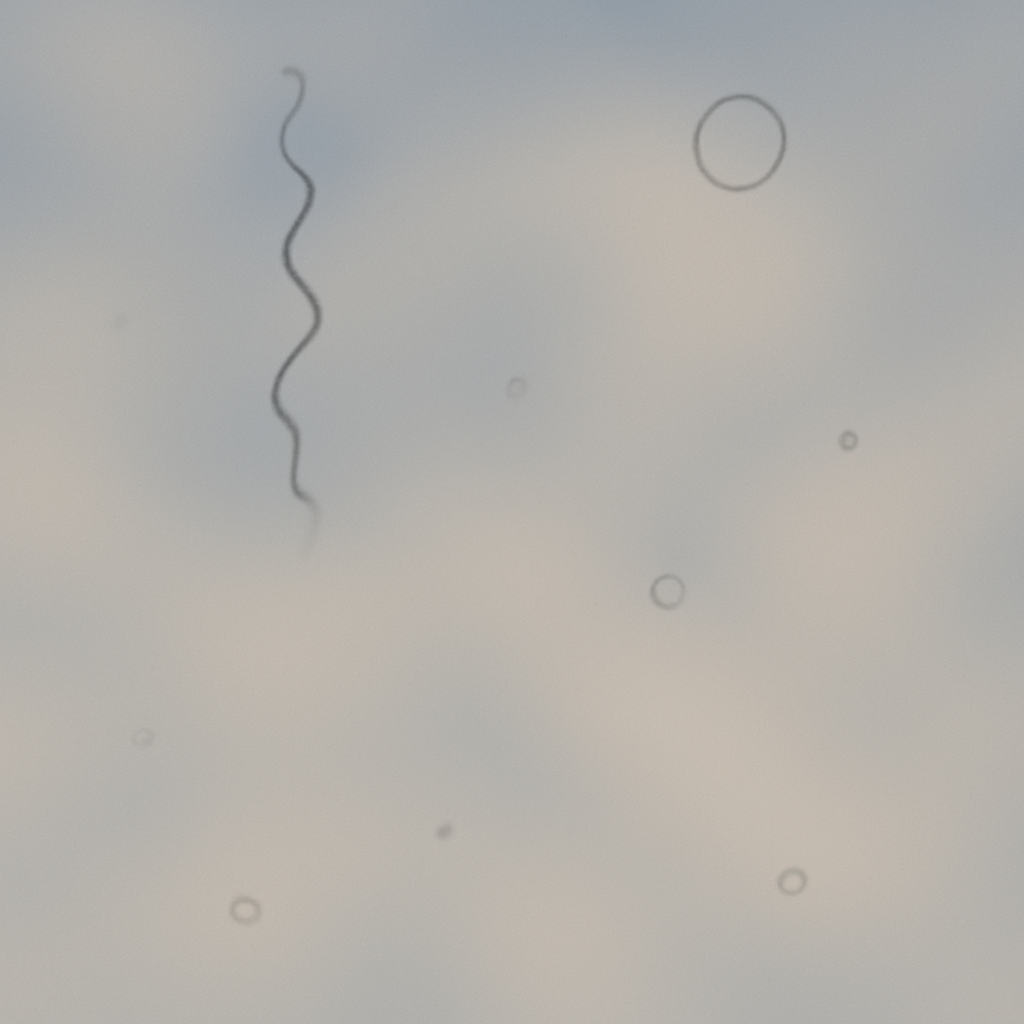

일상생활 중 갑자기 시야에 검은 점이나 실 같은 것이 떠다니는 경험을 한 적이 있으신가요? 이를 흔히 눈에 날파리 현상이라고 부릅니다. 마치 날파리가 눈앞을 날아다니는 것처럼 보인다고 해서 붙여진 이름입니다. 의학적으로는 ‘비문증(飛蚊症, Floaters)’이라고 하며, 대부분은 큰 문제가 없지만, 경우에 따라 심각한 안과 질환의 전조일 수 있어 주의가 필요합니다.

눈에 날파리 현상은 눈 속의 유리체(눈의 안쪽을 채우는 투명한 젤리 같은 물질)에 부유물이 생겨 빛이 망막에 도달할 때 그림자를 만드는 현상입니다. 이 그림자가 날파리, 점, 실, 거미줄처럼 보이며 시야에서 따라다니는 것처럼 느껴집니다. 보통 밝은 배경(하늘, 흰 벽)을 볼 때 더 잘 보입니다.